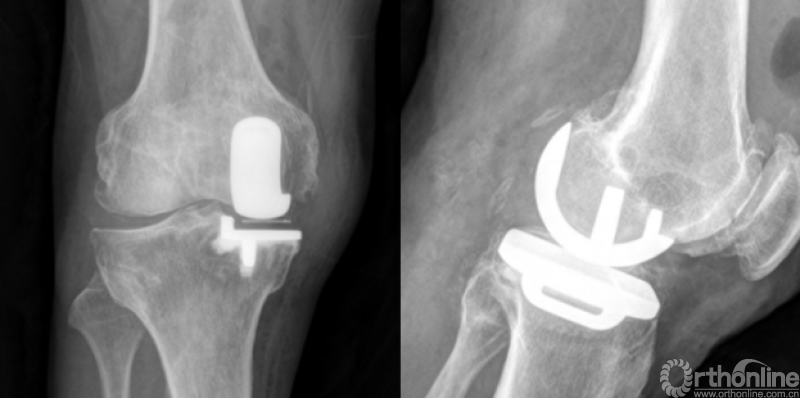

3、暴露ACL止点,标记ACL止点内侧缘。经过FAM外侧缘和ACL止点内侧缘(FAMA线)进行胫骨垂直截骨。截骨块上可见FAM(图中黄色三角形区域)。截骨块与假体匹配好。

4、术后影像学检查示,假体覆盖良好,假体外侧缘与Akagi线基本平行,未出现过度旋转。